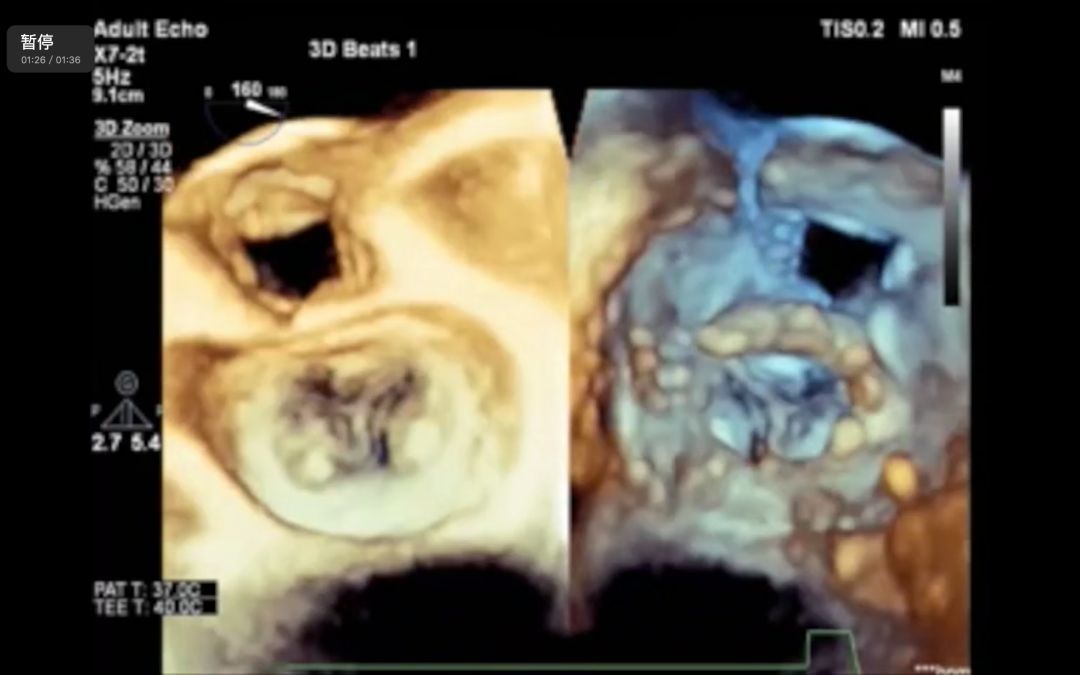

MitraFix®瓣膜的支架采用独特的单框架结构,有利于减少对左室流出道的影响。MitraFix®瓣膜采用牛心包瓣叶,其独有的镍钛合金框架设计将固定和防漏功能合二为一,有利于减小瓣膜压握后的尺寸和柔顺性。瓣膜依靠心室侧的两排共12个锚定爪与心房侧的D型伞状结构共同作用以达到稳固的锚定效果。这个设计同时也使得其压握后的直径小于其他同类产品。

MitraFix®的输送系统中内置了2个标示旋转方向和进入深度的超声标记,可以在超声影像中清晰地显示出与瓣环的相互位置关系。整个释放过程无需精确捕捉瓣叶或瓣下结构,因而对操作和定位精度的宽容度较大,这也是该产品只需依靠超声影像引导即可完成植入过程的主要原因。

潘湘斌教授指出,MitraFix®是能够以同一个瓣膜同时适用于经心尖和经股静脉输送系统的二尖瓣介入置换产品。其输送系统拥有独一无二的全超声引导设计,使得产品仅需要超声影像引导就可以完成植入定位,在超声下可以实时监测瓣膜状态,操作简便,学习曲线短。